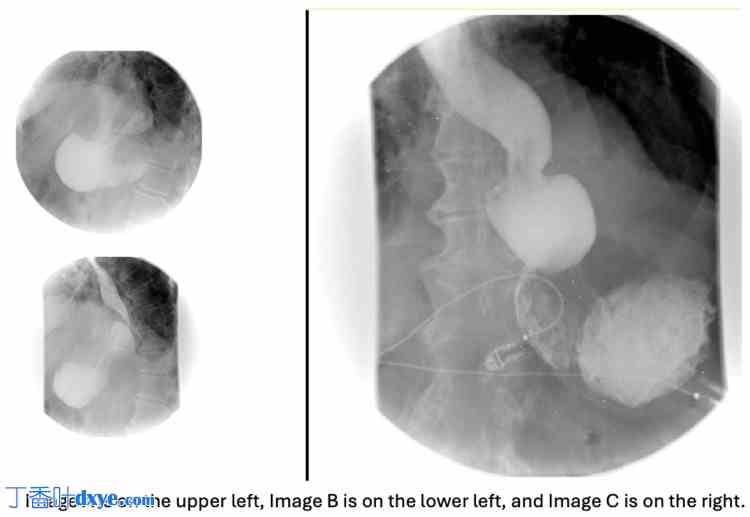

尽管住院第一天症状有所改善,但早餐后症状复发。尽管接受了止吐治疗,患者仍持续出现恶心和呕吐。置入鼻胃管进行胃减压。后续腹部X光检查显示明显的食管裂孔疝,大部分胃位于左半膈上方(图2)。钡剂食管造影显示一个大的滑动性食管裂孔疝,尽管患者禁食10小时,但胃内仍有液体和碎屑。钡剂食管造影也显示造影剂未从胃中排出,提示急性胃扭转(图3)。患者被诊断为嵌顿性食管旁疝和胃轴性胃扭转。

图2. 腹部X光片图像。

图像显示一个食管裂孔疝,大部分胃位于左半膈上方(标有星号)。